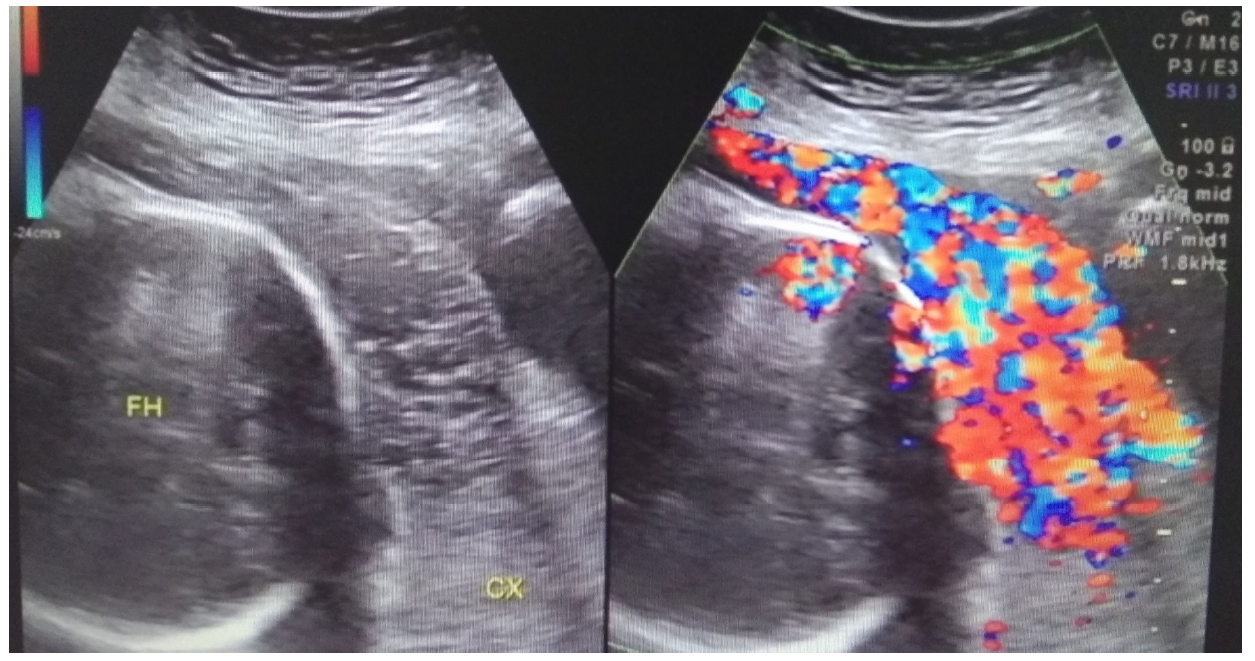

Placenta accreta spectrum occurred in both patients (Figure 3), and they gave birth prematurely between 32 and 33 weeks. Uncontrolled bleeding was the major challenge associated with the cesarean section. During the operation, the internal iliac artery was ligated, and local suturing was used to control bleeding. One woman (Case 6) successfully preserved her uterus and was diagnosed with placental increta. After using the hemostatic procedures described above, a subtotal hysterectomy was performed in Case 3 due to severe bleeding (8,000 mL) caused by placenta percreta. Then the placenta penetrated the myometrium and the serosal surface was confirmed.

Figure 3.

Figure 3.— A patient from the observation group during the third trimester. Abundant blood flow signals are apparent at the area of the placenta on color Doppler flow imaging. FH, fetal head; CX, cervix.